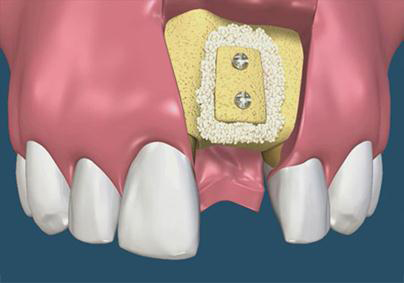

OsteoBiol - Kortikální lamina

Nový typ kortikální laminy (OsteoBiol) slouží k překrytí augmentačního materiálu při rozsáhlých 3D augmentacích a u velkých kostních

defektů. Jedná se o bovinní typ kortikální kosti.